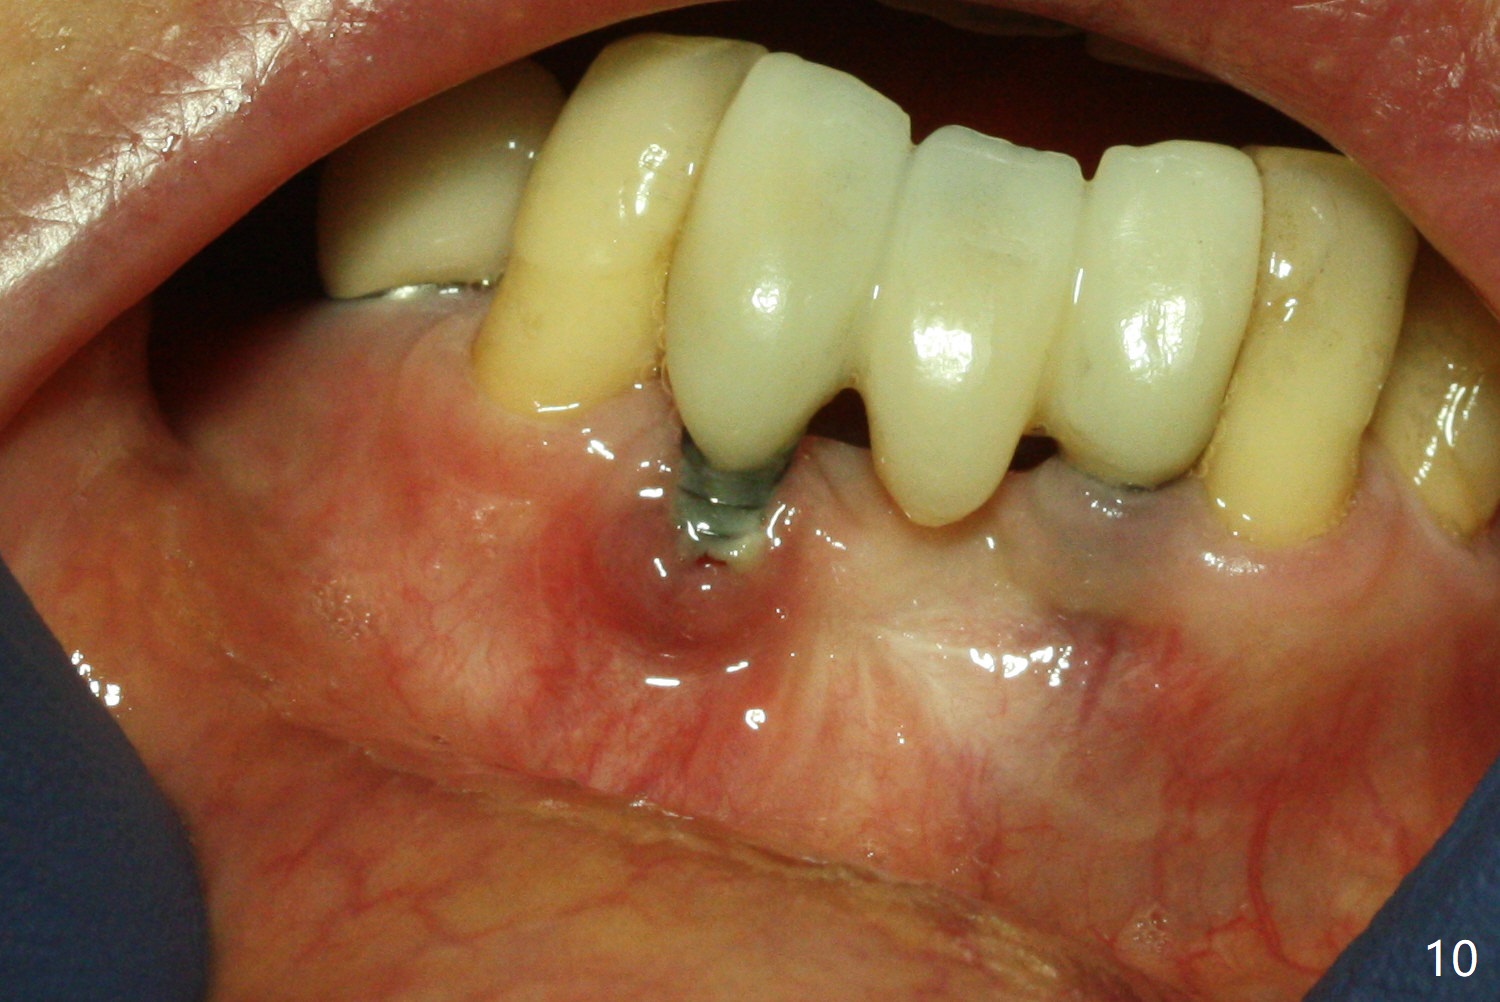

Fig.5 is taken following local anesthesia to show the exposed mesh, 22 days post placement. When the latter is removed, the exposed threads appear to be less (Fig.6, as compared to Fig.2). There is healthy granulation tissue growth apically (*). The patient is asymptomatic 1 month post mesh removal; there is no tenderness around exposed threads (Fig.7). Connective tissue graft is planned to cover the exposed threads through tunnel technique. Thread exposure appears less 3 months post mesh removal (Fig.8). There is infection when the region is not kept clean (Fig.9 (2.5 years post mesh removal)). The other 1-piece implant should have minor implant exposure (<). It appears that there is no thread exposure associated with the immediate implant at #28. Using smaller 1-piece implants (2.5 or 2.0 vs. 3 mm) with flap surgery should be able to prevent the complication. The 72-year-old phobic patient declines any further treatment. Two years later, she agrees to have treatment because of repeated infection (Fig.10). Impression has been taken for stent. After sectioning FPD and removing the infected implant (Tatum), a smaller implant will be placed in between the implants. If her vein is not too small, blood will be drawn for PRF.